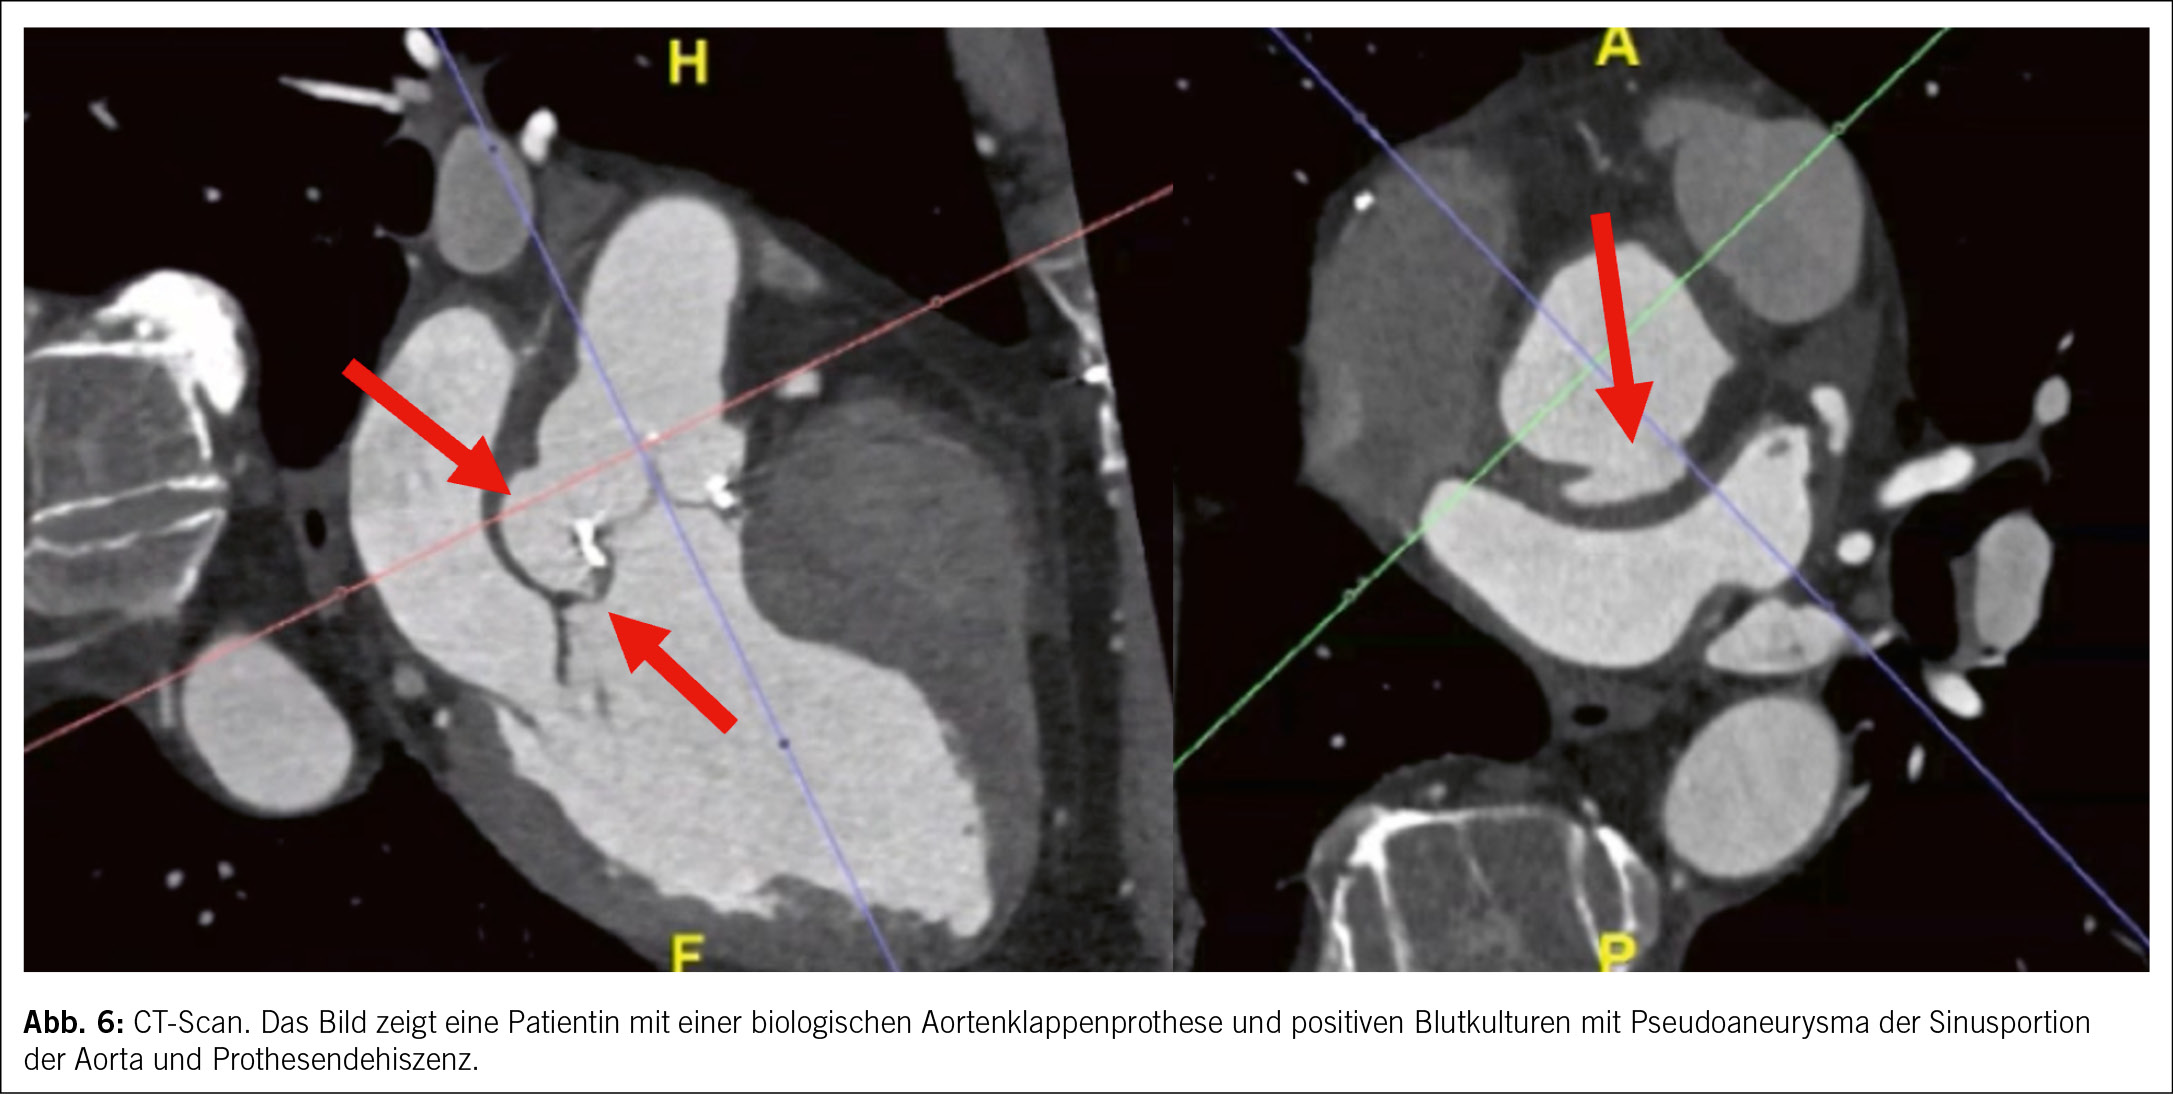

• Ein multimodaler Bildgebungsansatz wird dringend empfohlen. Neuere Studien haben gezeigt, dass die kardiale CT-Scan eine sehr gute diagnostische Aussagekraft für die Diagnose von Herzklappenläsionen und perivalvulären Komplikationen bei nativer Klappenendokarditis hat, während die PET-CT eine sehr gute Aussagekraft für die Diagnose von Endokarditis bei Herzklappenprothesen hat (9, 10), Abb. 6 und 7. Die Magnetresonanz Untersuchung ist nicht geeignet, um kardiale Vegetation oder Komplikationen zu erkennen, kann aber nützlich sein, um Fernläsionen zu entdecken.

• Für Patienten mit nativer oder prothetischer Herzklappenendokarditis wurden spezielle diagnostische Verfahren entwickelt. Insbesondere für den Fall, dass die Diagnose einer linksseitigen nativen oder prothetischen Herzklappenendokarditis nicht definitiv, aber möglich ist, empfiehlt die Leitlinie eine regelmässige Wiederholung der Blutkulturen (falls negativ oder zweifelhaft) und eine Wiederholung der Echokardiographie je 5–7 Tage; falls die Echokardiographie nicht diagnostisch ist, wird bei Patienten mit nativen Herzklappen ein CT-Scan empfohlen; bei prothetischen Herzklappen wird stattdessen ein kardiales CT-Scan oder PET-CT (oder, falls nicht verfügbar, ein White-Blood-Cell-SPECT) empfohlen. Wenn die Diagnose noch immer nicht definit ist, könnte ein weiteres Kriterium hinzugefügt werden, wenn eine extrakardiale Dissemination durch extrakardiale Bildgebungsmodalitäten festgestellt wird.

• Im Falle einer definitiven Endokarditis wird eine kardiale CT-Scan empfohlen, um eine paravalvuläre Komplikation zu erkennen, wenn die Echokardiographie nicht diagnostisch ist. Zusätzlich wird bei symptomatischen Patienten (Klasse I) eine extrakardiale Bildgebung zur Suche nach einer peripheren Dissemination empfohlen und kann bei asymptomatischen Patienten (Klasse IIb) in Betracht gezogen werden.